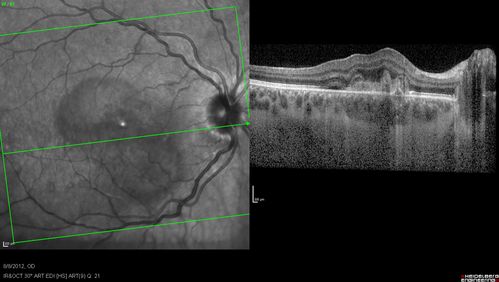

Punctate Inner Choroidopathy - PIC and Choroidal Neovascular Membrane - Right Eye - SD OCT

34-year-old woman with a change in vision in the right eye about eight days ago.  Her vision was hazy and she saw waviness in the vision.  She does have a history of aches and pains and she was diagnosed with Sjogren’s and 2 months ago she had some fevers and some sinus drainage and that went on for about two months.  She is a moderate myope.    OD 20/25, OS 20/20.